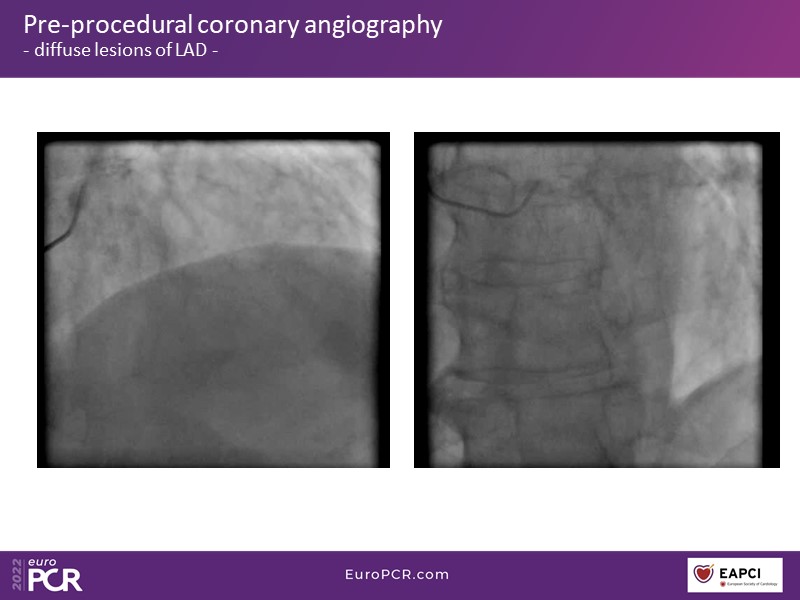

The challenge of the diabetic patient with diffuse coronary artery disease: how physiology can simplify things

Based on the didactic analysis of several practical cases, and also on the latest guidelines and study outcomes on the subject, learn in this EuroPCR 2022 session new management strategies to optimise PCI in diffuse coronary artery disease, new developments of the Optowire to support decision-making in patients with diffuse coronary artery disease, and get an update on the contemporary invasive diagnostic trends in these patients.